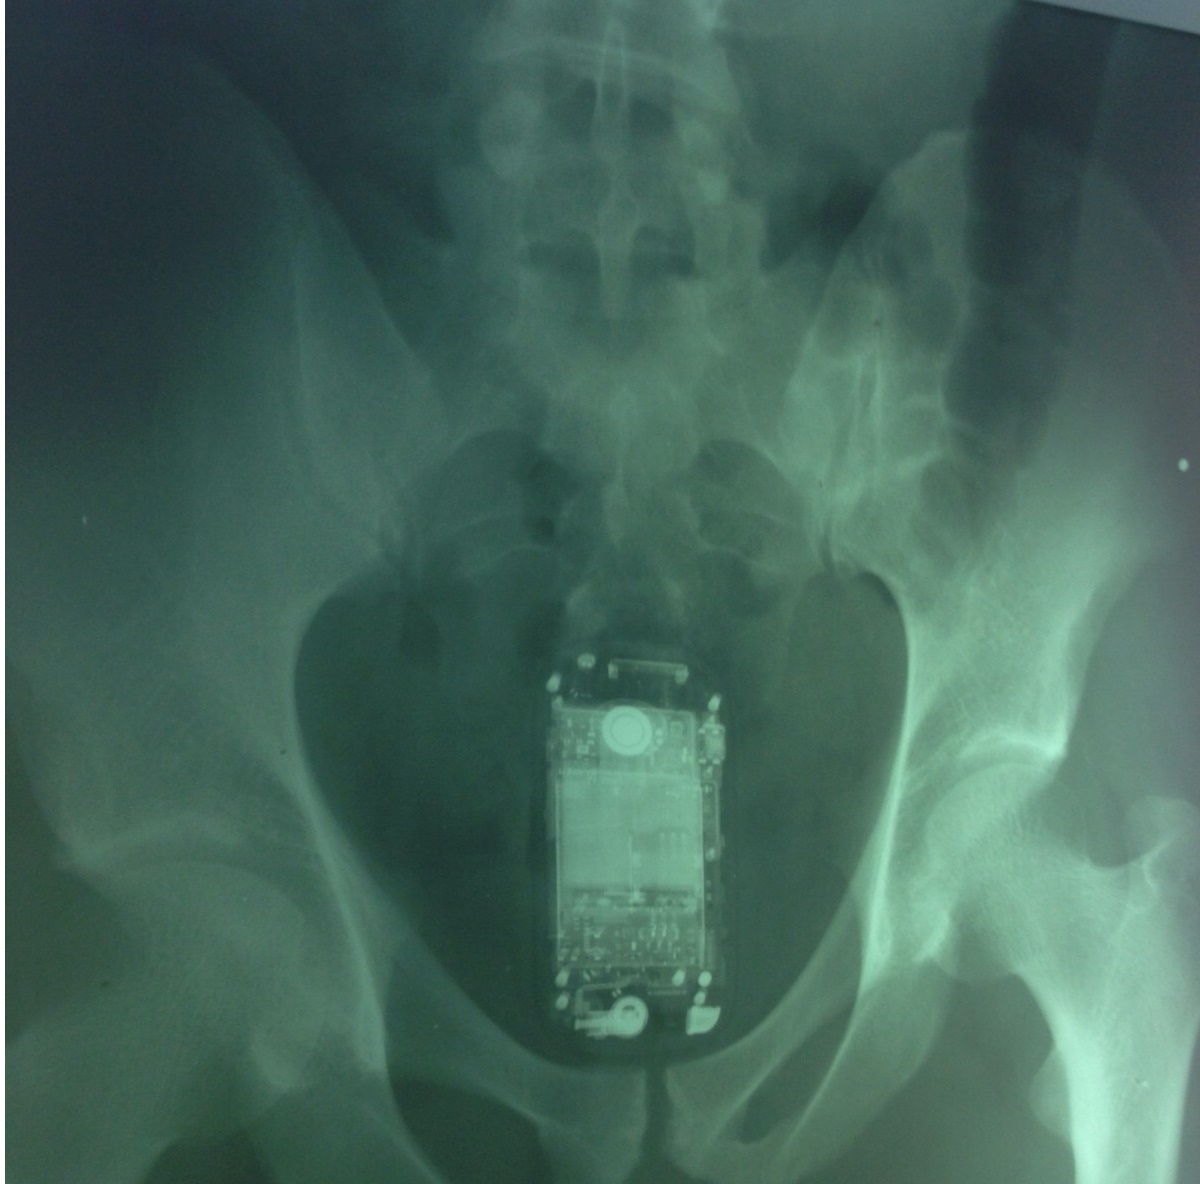

Detento esconde celular no ‘ânus’

Um detento identificado como Fabrício Melo B. Silva foi flagrado nesta semana na Unidade Prisional da cidade de Timon, no Maranhão, com um aparelho de celular smartphone escondido no ânus.

“O preso tinha escondido o aparelho telefônico dentro dele e depois que foi descoberto retirou da parte intima”, disse o funcionário, que não diz se identificado.

A tentativa frustrada foi descoberta pelos agentes penitenciários que utilizam detectores de metais durante uma revista de rotina.